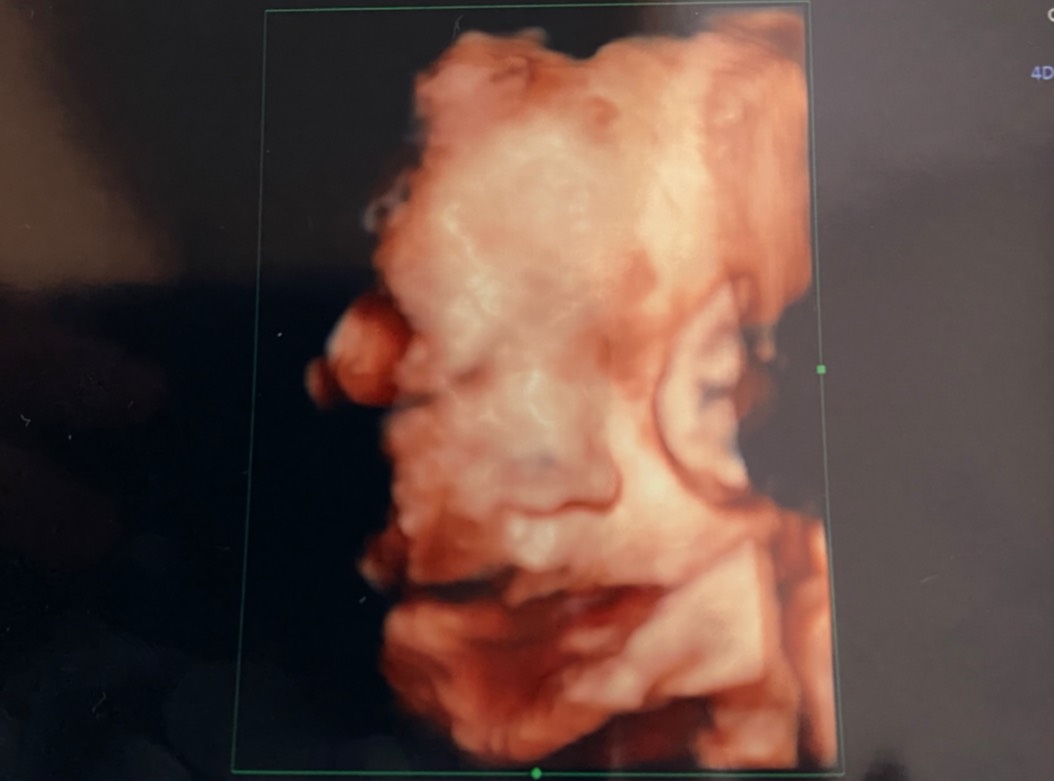

10週間ぶりの我が子のお顔

今日は10週間ぶりに、4Dエコーを頂けました!

今日のお顔はこんな感じでした。

エコー中、可愛い~~!!しか言ってなかった(笑)

我が子は可愛いです。ただ・・・

なんか顔つきが違う!(笑)

10週間も経てばそりゃ変わるか・・・(笑)

どっちにしろ可愛いのには変わりないですがね♡